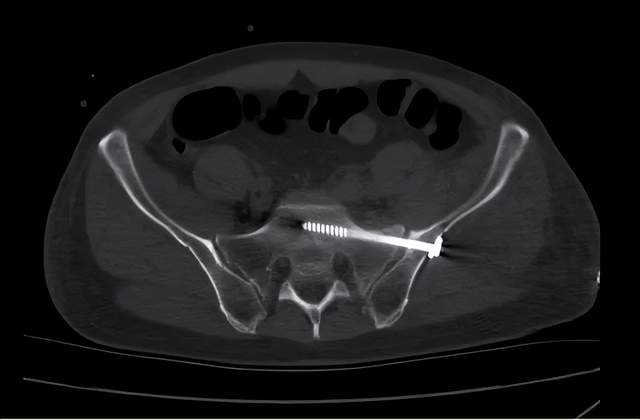

自 rahul vaidya 于 2012 年首次报道应用内置外固定架技术(infix)

骨盆前环不稳的内固定架(infix)固定术